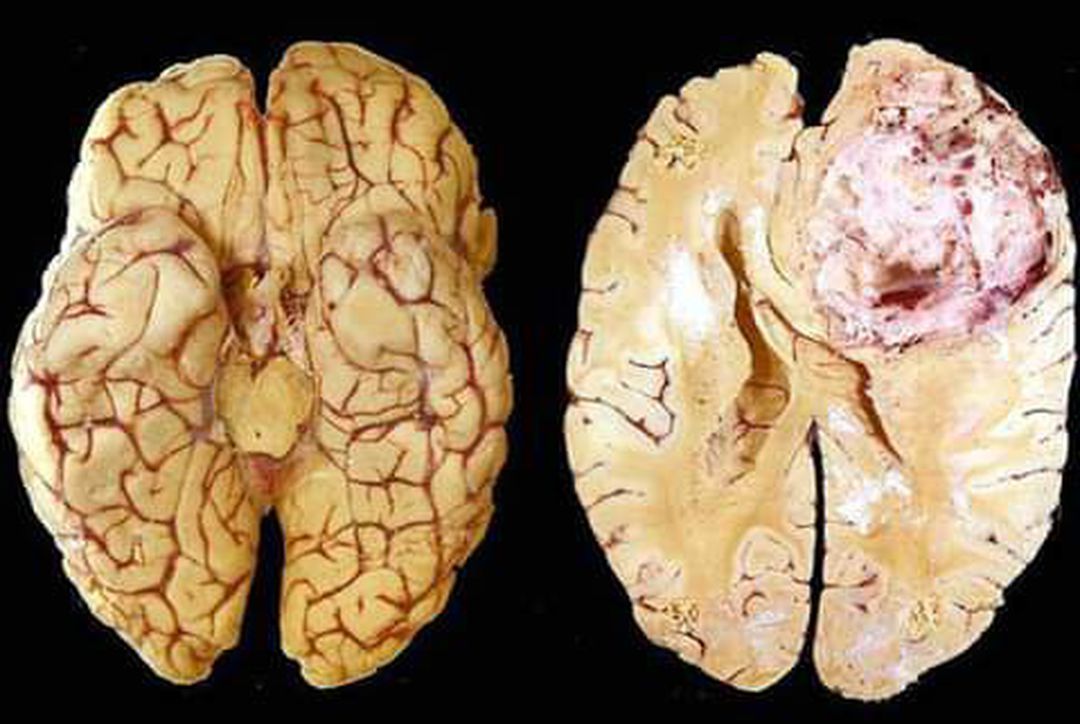

Glioblastoma multiforme is a grade IV astrocytoma; they are therefore generally aggressive, largely resistant to therapy, and have a corresponding poor prognosis. It represents the most common and malignant among glial tumors. These tumors are distinguished from anaplastic asteocytomas by the presence of endothelial proliferation of necrosis.